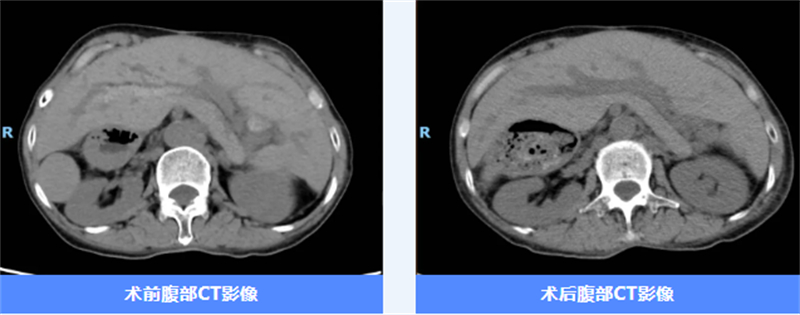

經過一系列細致的檢查,醫生發現唐阿姨存在肝內膽管多發結石、積氣并膽道梗阻,合并膽管炎。更讓人驚訝的是,唐阿姨還是一名“鏡面人”。何為“鏡面人”呢?“鏡面人”的出現概率非常低,大約為百萬分之一,他們的心臟、肝臟、脾臟、膽等器官的位置與正常人相反,即心臟、脾臟在右邊,肝臟、膽囊在左邊。

為做好這臺手術,肝膽胰外科團隊反復討論,做了充分的術前準備,從手術器械的選擇到術中可能遇到的復雜情況,都做了各方面預案。術中,肝膽胰外科團隊在麻醉科和手術室的密切配合下,克服思維定式,利用0.5厘米的“小切口”順利完成手術。術后經原有竇道進行兩次膽道鏡取石治療,就已取凈肝內膽管結石。

在快速康復理念的指導下,唐阿姨經過早期下床活動及飲食營養管理等一系列精心護理后,恢復良好,現已順利康復出院。